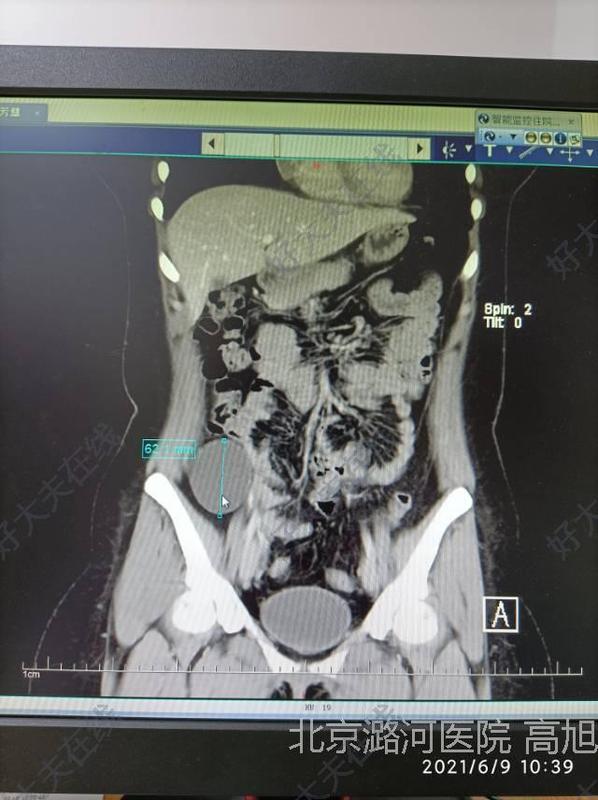

腹部腫物

治療前一位姑娘突然腹痛疼痛,過來就診發(fā)現(xiàn)右側(cè)腹腔里面1個像拳頭大小的包塊。她很糾結(jié),很著急,不知道怎么辦,還有點疼,害怕是個惡性腫瘤,天天擔(dān)心焦慮不已。她找到我們以后,我們很快完善了腸鏡以及腹部的CT檢查,會發(fā)現(xiàn)在右下腹闌尾外側(cè)有1個直徑約5cm左右的囊性包塊。治療中莫名其妙的的腹腔腫物,微創(chuàng)手術(shù)巧摘除一位年輕的姑娘突然腹痛疼痛,過來就診發(fā)現(xiàn)右側(cè)腹腔里面1個像拳頭大小的包塊。她很糾結(jié),很著急,不知道怎么辦,還有點疼,害怕是個惡性腫瘤,天天擔(dān)心焦慮不已。短時間各項準(zhǔn)備后,我們給她做了1個微創(chuàng)手術(shù)。手術(shù)中可以發(fā)現(xiàn)這個東西其實是長在腹膜外側(cè),是一個很薄很?。ㄐg(shù)后病理證實囊壁厚只有1毫米),可以說是薄如蟬翼的囊性包塊。我們用超聲刀和腹腔鏡器械很仔細(xì)的慢慢的剝下來,剝離過程就像刀尖上的舞蹈,因為這個囊腫壁很薄,稍微用力就有可能破裂?;旧鲜且淮缫淮鐝母贡谏蟿兿聛?。手術(shù)過程很順利,在精心切下來后囊腫沒有破裂,避免了腫物向腹腔內(nèi)進(jìn)行播散的可能性。我們也沒有腹壁再切口,而是通過腹腔鏡戳卡把腫物取出來,讓她肚子沒有明顯瘢痕,讓這個愛美的姑娘可以繼續(xù)美下去。治療后治療后7天今天病理回來是一個良性的囊腺瘤。我們很欣慰,通過我們的技術(shù),用/&/gldquo;細(xì)心+耐心/&/grdquo;幫助她康復(fù)了?

高旭醫(yī)生的科普號2021年06月09日760